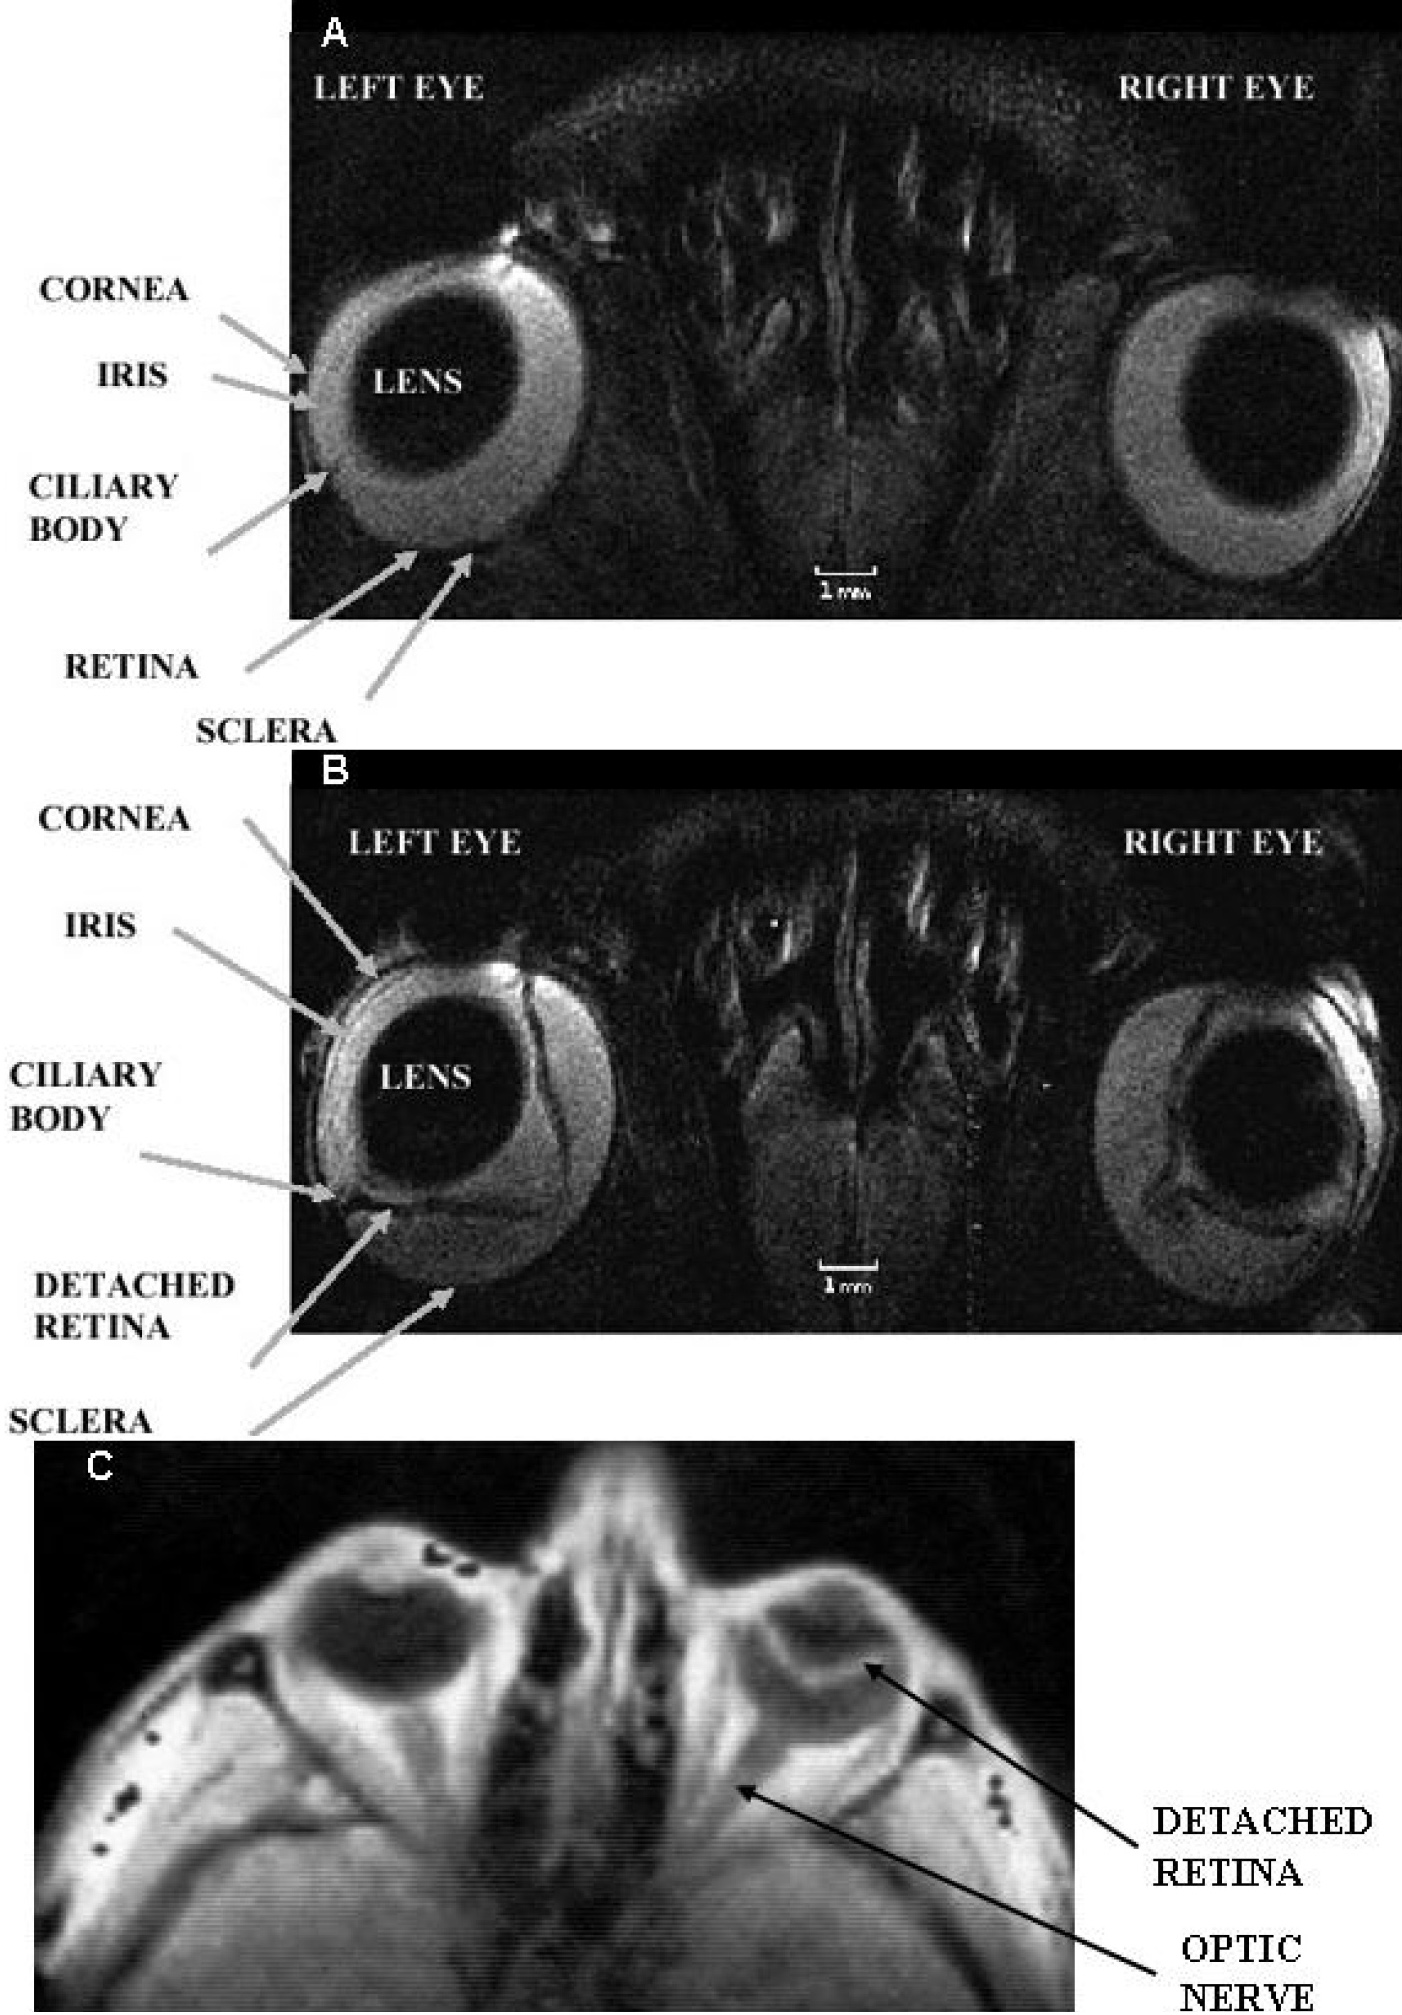

Figure 2 of Fanea, Mol Vis 2012; 18:2538-2560.

Figure 2. Selected regions of in vivo MRI images of the rat (A and B and the human C eye. Eye structures such as the lens, cornea, iris, ciliary body, retina and sclera are visualized. In A both rat eyes are normal. The left rat eye in B is at peak of experimental autoimmune uveitis and the right rat eye in the same figure shows post-peak of disease. The spatial resolution of each MRI rat image was 60×60×700 μm3 and the acquisition time was 30 min. The left human eye in C: shows no retinal detachment, while the right human eye in the same figure shows a large retinal detachment. The MRI images in A and B are T2-weighted, while that in C is T1-weighted. The images in A and B were reproduced from [38] while that in C: from [43] with permissions from John Wiley & Sons and Elsevier Ltd respectively.